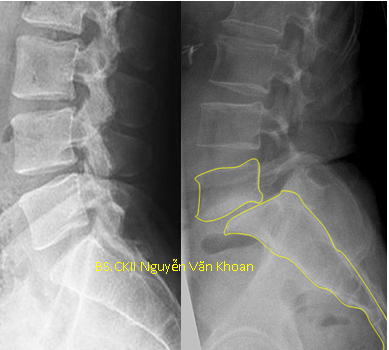

Hình X quang cho thấy bệnh nhân bị trượt đốt sống thắt lưng L5/S1 đã được mổ nắn chỉnh, đặt dụng cụ ốc chân cung với 2 thanh nối dọc, hàn liên thân đốt bằng nêm PEEK.

Có nhiều phương pháp mổ để điều trị trong trường hợp này. Phẫu thuật nắn chỉnh trượt, đặt dụng cụ, hàn xương liên thân đốt lối sau cho kết quả tốt và được làm nhiều nhất hiện nay, tuy nhiên dụng cụ lại đắt tiền.

Việc nắn chỉnh là cần thiết để sửa sự biến dạng tư thế xấu cho bệnh nhân. Cố định bằng dụng cụ và hàn xương giúp giữ sự vững chắc cho cột sống về sau. Song song với việc nắn chỉnh, hàn xương và cố định dụng cụ thì việc giải ép rễ thần kinh là cần thiết.